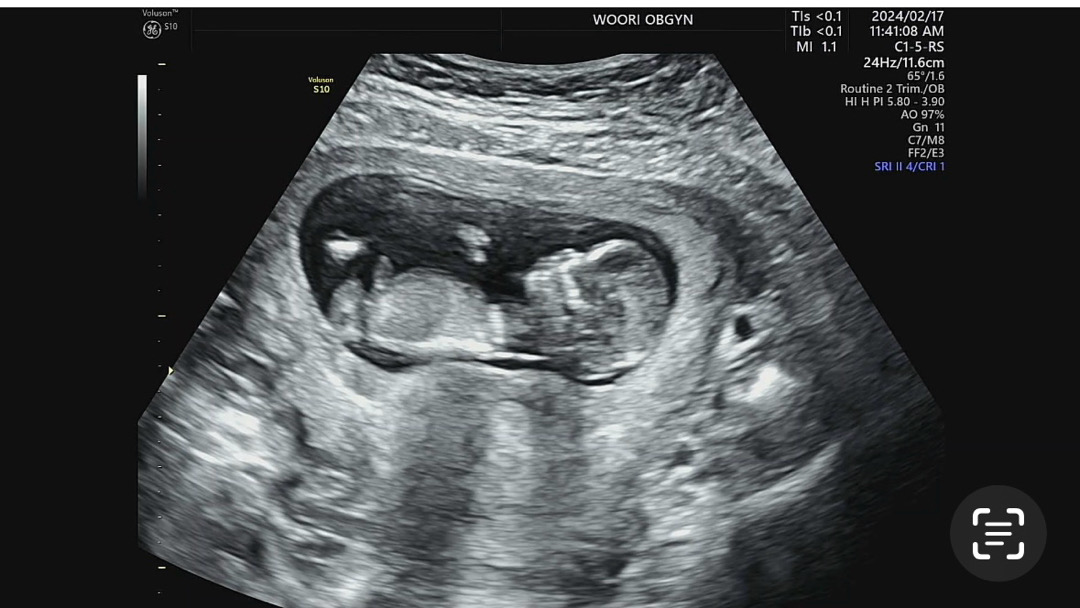

12주3일 각도법한번봐주세요ㅠㅠ

유투브보면서 각도법찾아봐도 도저히 모르겠네요 ㅠㅠㅠ보이시는분계신가용..?